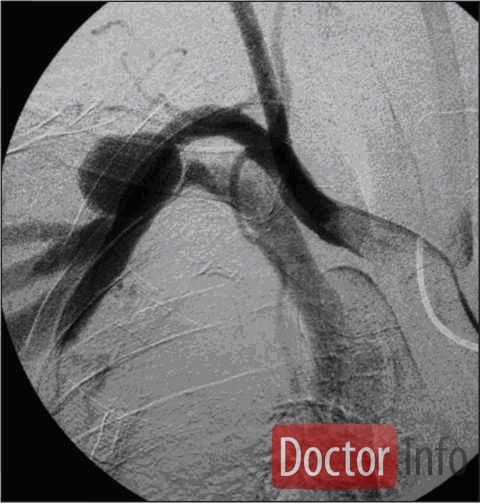

Диагноз ставится  после осмотра врачом и проведения ряда дополнительных методов исследования. С помощью стетоскопа, приставленного к месту фистулы, слышен машинный шум. Окончательно диагноз подтверждается после проведения ультразвукового дуплексного сканирования ( сочетание допплеровского ультразвукового сканирования с традиционным ультразвуковым исследованием), ангиографии или МР-ангиографии.

Медицинские процедуры, проводимые при заболевании артериовенозная фистула: Ультразвуковое дуплексное сканирование, Ангиография, Магнитно-резонансная ангиография